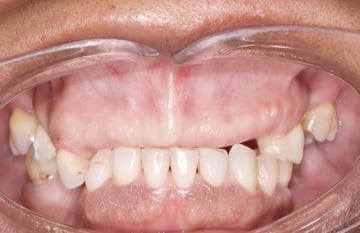

At the initial examination, the patient presented with a terminal dentition requiring comprehensive evaluation. Cases like this demand disciplined attention to prosthetic fundamentals before any surgical decisions are made.

Rather than rushing into implant placement, our team first focused on the core clinical questions: establishing vertical dimension, confirming restorative space, evaluating jaw relationships, and determining the ideal esthetic tooth position. These basics ultimately dictate the predictability of advanced terminal dentition treatment.